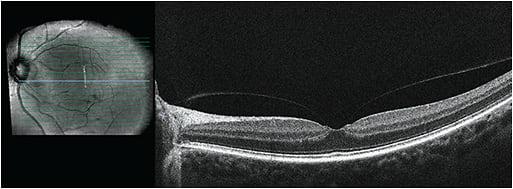

- Screen for pre-existing retinal disease: Perform a dilated peripheral retinal assessment prior to initiating miotic therapy and consider repeating this procedure periodically during the first 2-3 months of treatment in high-risk patients. Carefully assess the status of the vitreous since the absence of a PVD likely poses a greater risk for complications. Consider macular optical coherence tomography screening on all patients prior to initiation of miotic therapy to detect subclinical vitreomacular traction (Figure 2).

Figure 2. Vitreofoveal traction. - Avoid in patients at high risk for rhegmatogenous retinal detachment: Use with caution in individuals at high risk for detachment, such as those with lattice (especially if perivascular or radial; Figure 3), high myopia (or former high myopes who have undergone refractive surgery), aphakia, personal or family history of retinal detachment, genetic disorders such as Stickler syndrome, and patients with history of significant trauma thought to have altered the structure of the vitreous or retina.4,28 It may be worthwhile to refer patients at high risk for detachment to a retinal specialist for assessment and possible prophylactic barrier laser prior to initiating miotic therapy if it is necessary (Figure 3).19,21

Figure 3. Perivascular lattice before and after prophylactic barrier retinopexy. - Avoid in patients with vitreofoveal traction: Miotics are probably best avoided in patients with vitreofoveal or vitreomacular traction (Figure 2). Smaller zones of macular attachment likely impose a greater risk for complications since the tractional force per area increases as the size of the vitreomacular adhesion zone decreases.